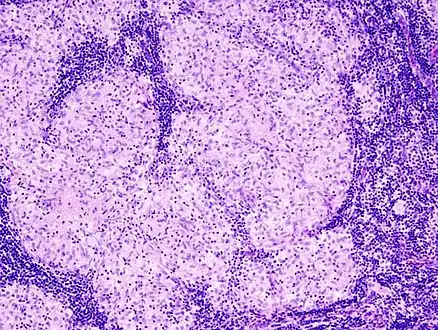

Histopathology

Sarcoidosis is characterized by the formation of non-necrotizing ("non-caseating") granulomas in various organs and tissues.[96] Giant cells, specifically Langhans giant cells, are often seen in sarcoidosis.[97] Schaumann bodies seen in sarcoidosis are calcium and protein inclusions inside of giant cells as part of a granuloma.[98] Asteroid bodies can be seen in sarcoidosis.[98] Hamazaki–Wesenberg bodies can be seen in lymph nodes and more rarely in lung biopsies with sarcoidosis and are inclusion bodies of lysosomes with protein, glycoprotein and iron.[99]